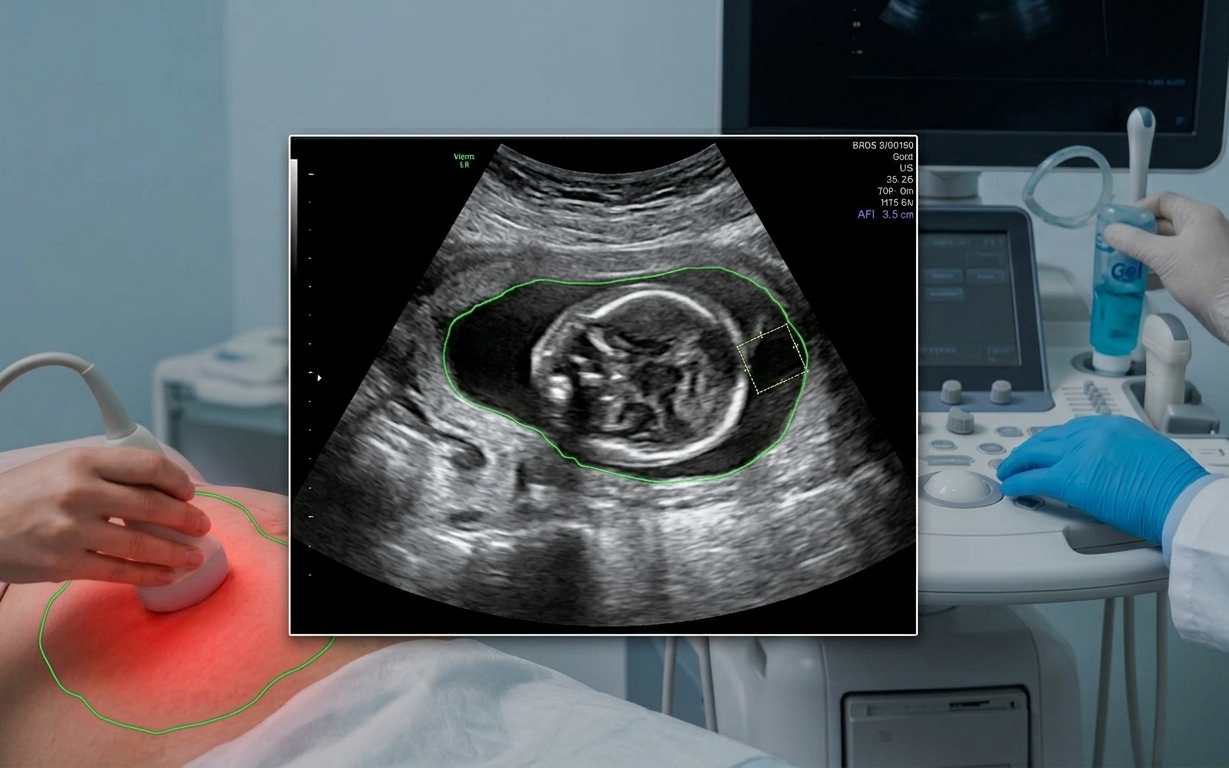

Các bác sĩ sẽ giám sát chặt chẽ sức khỏe tim mạch trong các buổi khám thai định kỳ.

Những điều chỉnh này là thiết yếu cho một thai kỳ khỏe mạnh nhưng việc theo dõi là rất quan trọng. Các bác sĩ sẽ giám sát chặt chẽ các chỉ số tim mạch trong các buổi khám thai định kỳ, cho dù mẹ bầu có bệnh lý tim mạch tiềm ẩn hay có nguy cơ gặp các vấn đề tim mạch liên quan đến thai kỳ.